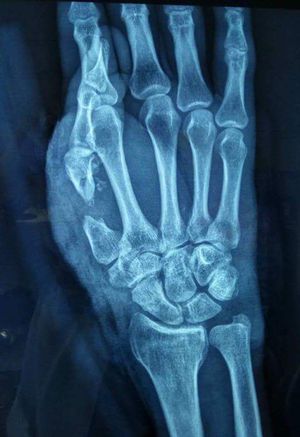

Hand

man arrived at the hospital (with ambulance) with his hand flexed

Fracture base of 1st metacarpal

Bennetts fracture??

No..just 1st metacarpal bone